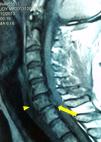

Caso 2Varón de 73 años de raza blanca, con antecedentes de hipertensión tratada con enalapril y múltiples caídas por síncopes de repetición. Fue traído al hospital por nueva caída, sin clínica neurológica, pero se diagnosticó por TC fractura del arco posterior de C6 no desplazada. Fue dado de alta con tratamiento conservador. A los 3 días presentó otra caída y fue traído de nuevo, esta vez presentaba una tetraplejía con un nivel neurológico de T4. Se realizó una resonancia magnética nuclear (RM) urgente que evidenció una herniación traumática de disco C5-6, con contusión medular asociada (fig. 2). Ingresó en la unidad de cuidados intensivos donde, debido a una capacidad ventilatoria subóptima, se decidió iniciar ventilación mecánica con intubación orotraqueal. Tras la obtención del consentimiento del paciente, realizamos un manejo anestésico idéntico al descrito en el caso 1, con la peculiaridad de que este paciente presentó una excelente tolerancia a la técnica de intubación debido probablemente a la incapacidad tusígena asociada a su lesión. La exploración neurológica tras la intubación se mantuvo idéntica. Posteriormente, se realizó cirugía de fijación cervical pero la evolución fue desfavorable, falleciendo a los 5 días.